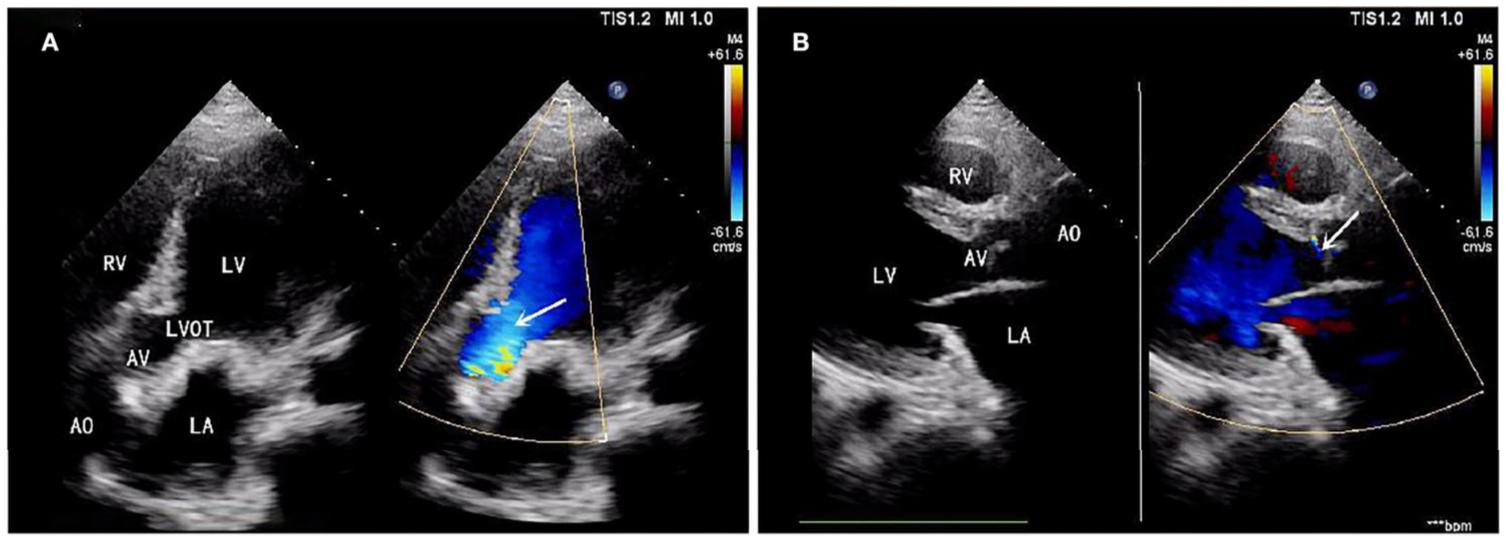

术后病理学显示主动脉壁中层平滑肌萎缩和变性、局灶性玻璃体变性、粘液样变性和钙盐沉积(图4)。术后2个月的随访超声心动图显示,左心室流出道局部梗阻明显改善(术后左心室流出程梯度为7 mmHg),主动脉瓣返流轻微(图5)。在术后1年的随访中,手术效果仍然是积极的,并且没有任何明显的恶化进展。

图5.(A)左心室流出道阻塞消失(LVOT梯度为7mmHg)。(B)轻微主动脉瓣返流。